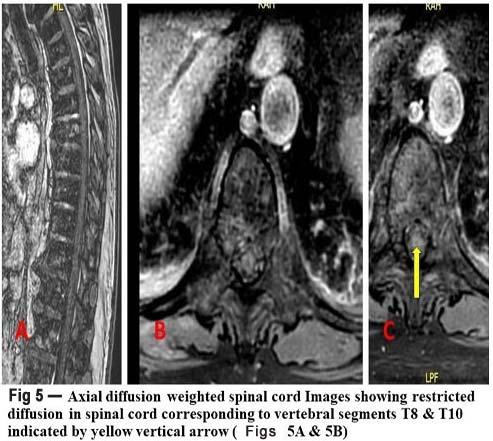

Routine blood investigations, ECG, chest Xray, CT scan and MRI of the face (including orbits) and brain were done (Fig 1).